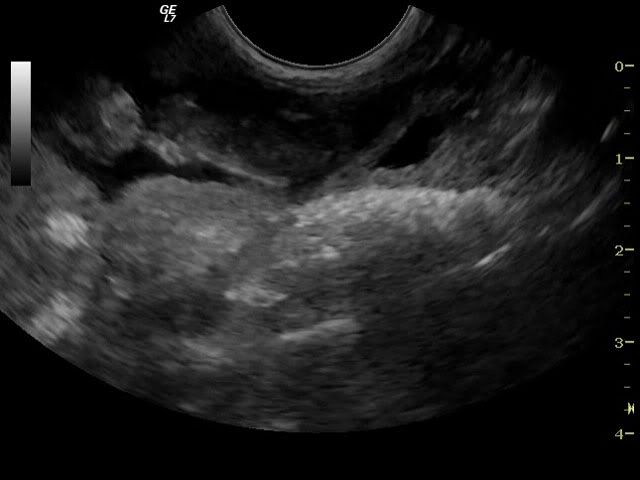

og endnu en :D

med streger